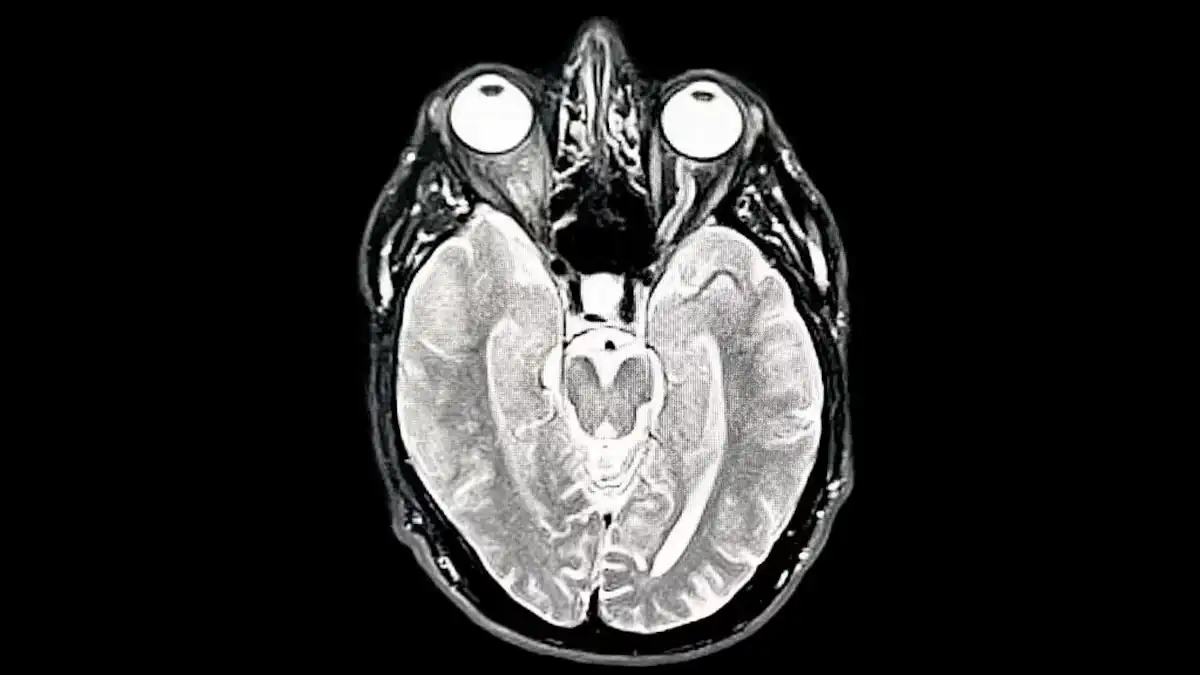

Envejecimiento inicial (66 – 83 años):

El cerebro empieza a reorganizarse. Algunas regiones trabajan de manera más independiente y la comunicación entre ciertas áreas disminuye, pero no se trata de una caída abrupta.

Envejecimiento avanzado (83+):

Los patrones anteriores se intensifican. Las redes se fragmentan un poco más y la eficiencia baja gradualmente, aunque existen menos estudios en personas de esta edad.